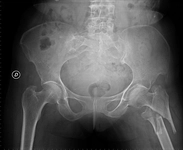

Kalça Emarı Nedir?Kalça emarı, manyetik rezonans görüntüleme (MRG) teknolojisi kullanılarak kalça ekleminin ve çevresindeki dokuların detaylı görüntülerinin elde edilmesi işlemidir. Bu görüntüleme yöntemi, özellikle kalça ekleminde meydana gelen yaralanmalar, artrit, tümörler ve diğer patolojilerin tanısında büyük öneme sahiptir. Kalça emarı, radyasyon kullanmayan bir görüntüleme tekniği olması nedeniyle, hastalar için daha güvenli bir seçenek sunar. Kalça Emarı Çekimi SüresiKalça emarı çekimi süresi, birçok faktöre bağlı olarak değişiklik gösterebilir. Genel olarak, kalça emarı çekimi için gereken süre yaklaşık 20 ila 40 dakika arasında değişmektedir. Ancak bu süre aşağıdaki etkenlere bağlı olarak uzayabilir veya kısalabilir:

Sonuç ve DeğerlendirmeKalça emarı çekimi, genellikle 20 ila 40 dakika arasında bir süre almaktadır. Ancak, hastanın durumu, kullanılan teknoloji ve ek görüntüleme gereksinimleri gibi faktörler bu süreyi etkileyebilir. Çekim öncesi hazırlıklar ve çekim sırasında dikkat edilmesi gereken hususlar, hastaların emar sürecini daha konforlu hale getirebilir. Sonuçlar, doktor tarafından değerlendirilerek hastaya detaylı bir bilgi sunulacaktır. Ekstra BilgilerKalça emarı çekimi, genellikle acısız bir işlem olarak kabul edilir. Ancak, bazı hastalar dar alanlarda yatmanın rahatsız edici olabileceğini belirtmişlerdir. Bu nedenle, hastaların endişeleri olduğunda, önceden doktorlarıyla bu konuyu görüşmeleri önerilmektedir. Ayrıca, bazı hastalar için sedasyon veya anksiyolitik ilaçlar kullanılması gerekebilir, bu durumda hastaların yanlarında bir refakatçi bulundurmaları önemlidir. |